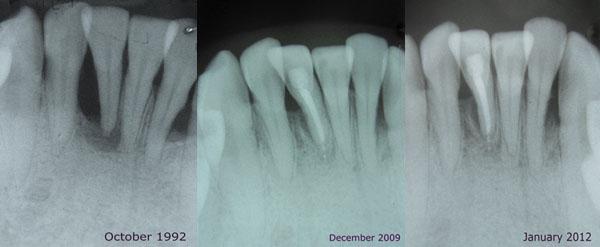

Patient with severe periodontitis improves with microbial treatments and one surgery.